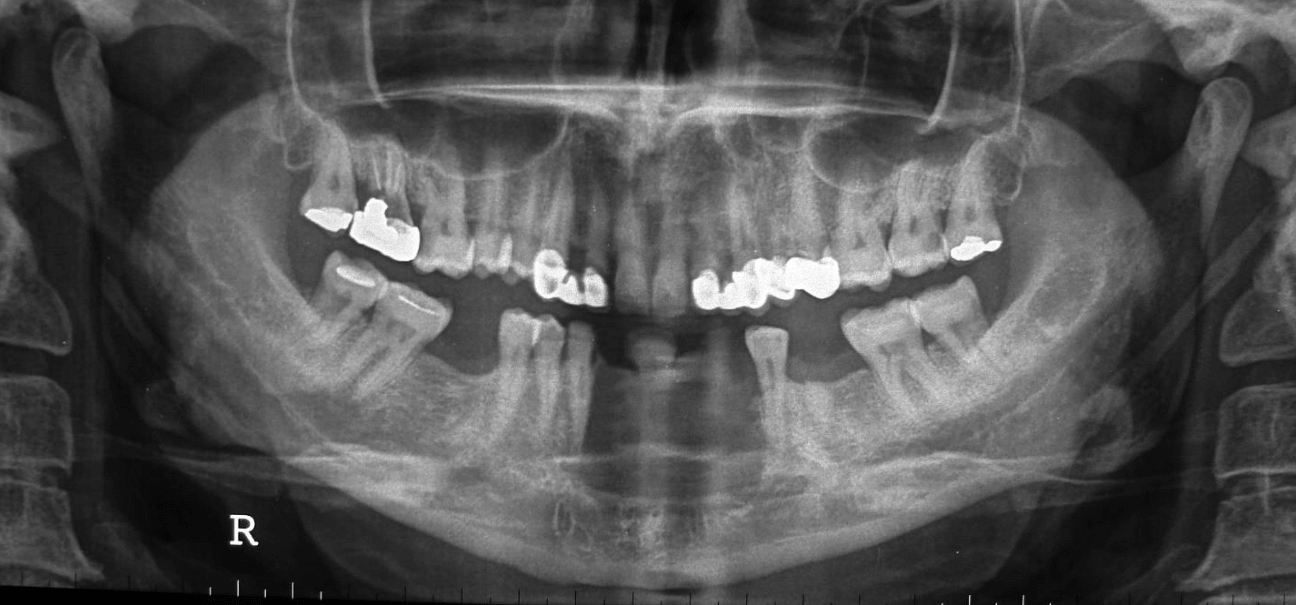

Preoperative radiographic examination including panoramic X-ray and C.T for evaluation of mandibular bone invasion by the lesion and evaluation of the neck lymph nodes (Figure 2A, B, C). Both the mandibular bone and neck lymph nodes were free. Whole body scan with Technetium-99m radiopharmaceuticals imaging was negative (Figure 2D). Clinical stage according to TNM system was T1N0M0.